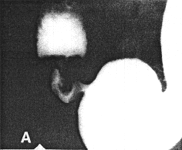

Case 28.2 J.C., 63 year old male, was a know case of ethanol abuse and liver cirrhosis. Radiographic examination showed a marked degree of constant contraction of the pyloric sphincteric cylinder, which contained prominent, irregular, immobile mucosal folds (Fig. 28.2 A-D).

![]() | |

| Fig. 28.2 A-D. Case J.C. Constant contraction of sphincteric cylinder with absent cyclical activity. Irregular, immobile folds in cylinder | |

Peristaltic waves were normal in the remainder of the stomach, but stopped abruptly at the commencement of the cylinder, which showed total absence of cyclical contraction and relaxation. Endoscopy revealed chronic "antral" gastritis; a few small erosions were noted in the first part of the duodenum.